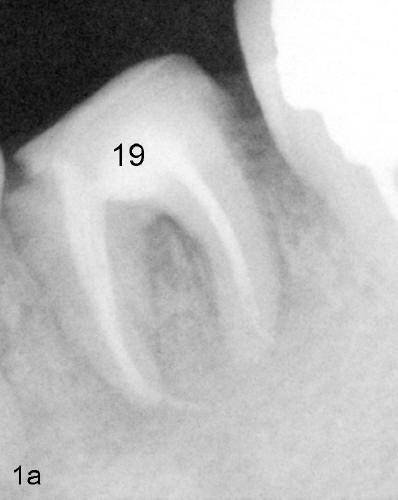

Traditional X-ray can still shows PARL (red <) and abnormal communication (black lines) before (Fig.1a) and after (Fig.1b) being labeled, as compared to CT image on the far right side, back to original article